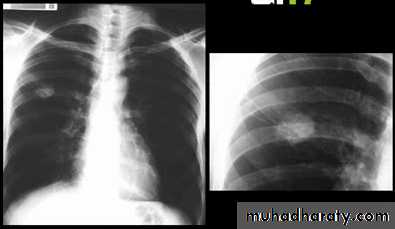

Miliary Tuberculosis. A cone-down view of a frontal radiograph demonstrates innumerable micronodular opacities characteristic of micronodular (miliary)

interstitial disease.

Transbronchial biopsy demonstrated caseating granulomas containing acid-fast bacilli.

Miliary TB

a frontal radiograph demonstrates innumerable micronodular opacities characteristic of micronodular (miliary) interstitial disease. Transbronchial biopsy demonstrated caseating granulomas containing acid-fast bacilli.